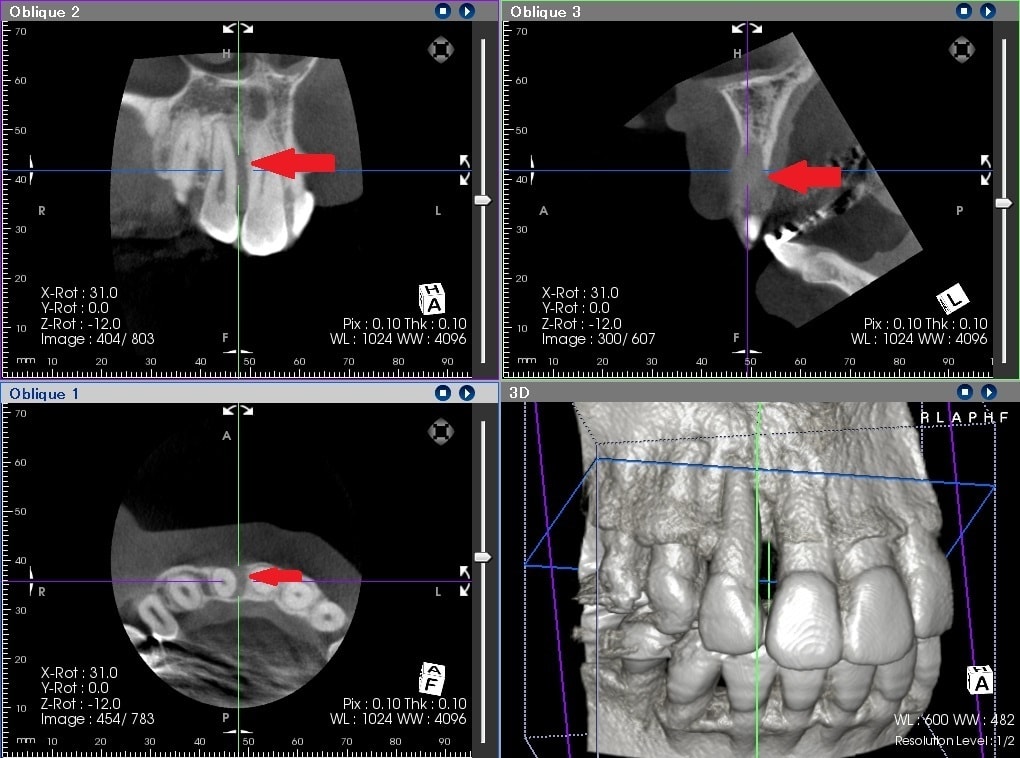

治療前は、赤の矢印で示すように歯の周りに黒いところがあることが分かるかと思います。簡単に言うと、骨が溶けた状態になります。

通常、歯周ポケットと呼ばれる歯と歯茎の間の溝は3㎜程度なのですが、10㎜を超える歯周ポケットがありました。CTは、手術前に骨の欠損形態を的確に把握できるため、歯周病の治療にも非常に有用です。

歯周病の基本的な治療を行い、その後に、歯周組織再生療法という失われた歯の周りの組織を再生させる手術を行って約2年のレントゲンになります。

青の矢印で示すように、治療前黒かった部分が、白くなってきていることが分かるかと思います。失われた歯周組織の再生が促されていることが推測されます。CTにおいても歯の周囲の失われた骨が再生してきていることが、分かるかと思います。